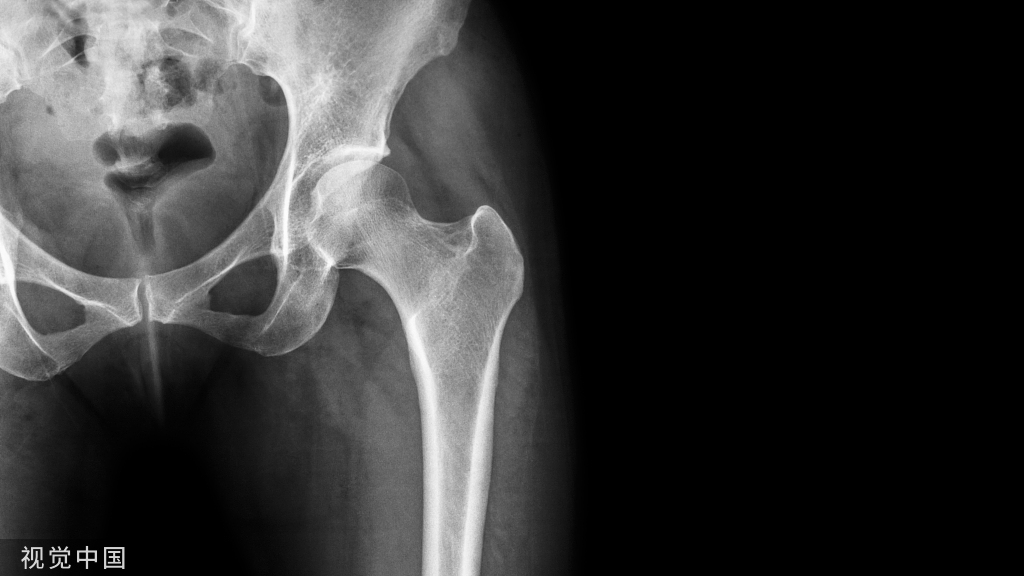

随访期间无陶瓷碎裂,5(5/85,5.9%)髋出现异响(吱吱声),3髋出现假体周围骨溶解(2髋位于股骨柄周围,Gruen分区 1和 7区,图1;1髋位于髋臼周围,DeLee -Charnley分区 2区,图2)。1例因Vancouver B2型股骨假体周围骨折而翻修(图3);1例合并系统性红斑狼疮的患者因假体周围关节感染而接受了清创术。任何原因导致再次手术的存活率为92.4%(95%置信区间为82.4%至100%)。

图1.骨溶解位于Gruen分区 1和 7区